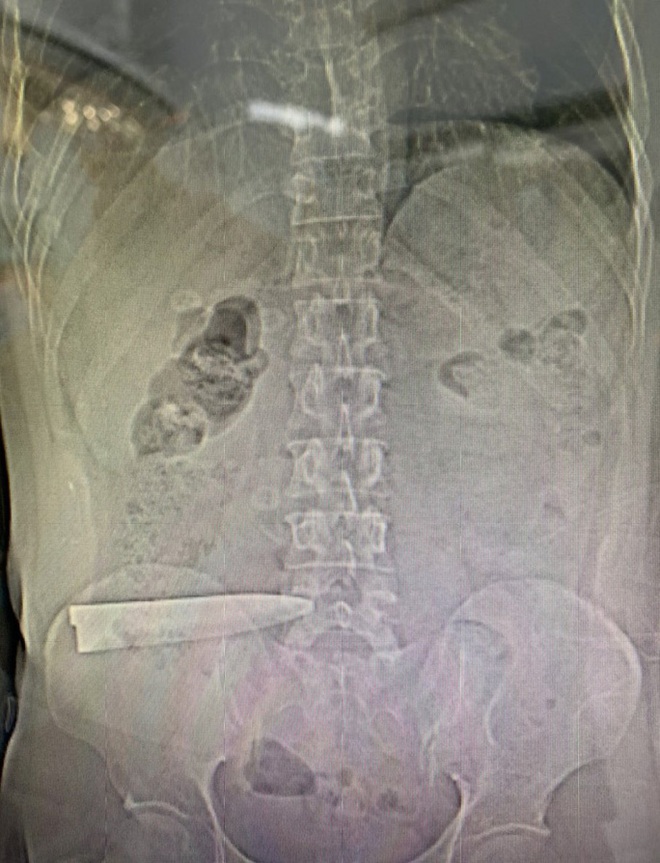

Kết quả chụp CT bệnh nhân cho thấy có lưỡi dao nằm trong ổ bụng, không có cán dao, xuyên ruột, tĩnh mạch chậu bên phải, mũi chạm vào cột sống.

Tối 30-12, bệnh nhân đưa vào cấp cứu trong tình trạng rất nguy kịch với vết thương thấu bụng. Kết quả chụp CT cho thấy có lưỡi dao nằm trong ổ bụng, không có cán dao, xuyên ruột, tĩnh mạch chậu bên phải, đầu lưỡi chạm vào cột sống .

Bác sĩ Mai Hóa, Trưởng Khoa Ngoại tổng hợp Bệnh viện quận Thủ Đức, cho biết bệnh nhân bị lưỡi dao đâm sâu đến tận cột sống làm rách manh tràng 2 lỗ, tổn thương rách toàn bộ khẩu kính ruột non cách góc hồi manh tràng 70cm, thủng tĩnh mạch chậu chung bên phải, lưỡi dao chỉ dừng lại khi đụng vào cột sống thắt lưng.

Sau hơn 5 giờ phẫu thuật, dị vật lưỡi dao gãy cán được rút ra, bệnh nhân qua cơn nguy kịch, sinh hiệu ổn, tiếp tục theo dõi. Bệnh nhân được cứu sống trong gang tấc nhờ sự phối hợp nhanh chóng, nhịp nhàng của nhiều y bác sĩ liên chuyên khoa.